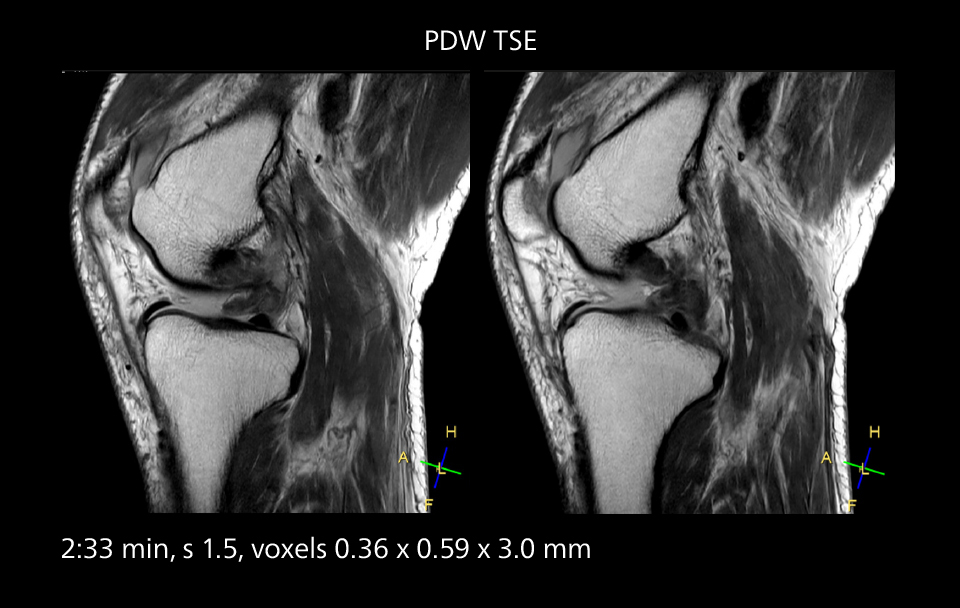

Images showing a posterior cruciate ligament (PCL) tear, a detached medial collateral ligament (MCL) on the tibial side and an intact anterior cruciate ligament (ACL). SmartPath to Elition X helped reduce scan time compared to previous imaging while maintaining resolution.

Sannodai Hospital radiologists had been very satisfied with their Ingenia 3.0T with Compressed SENSE, however after acquiring SmartPath to Elition X they have demonstrated improved image quality and even higher speeds in imaging studies throughout the body, according to Dr. Makuuchi. “Generally, we were impressed by seeing that images are very sharp and have higher SNR than we used to get with our Ingenia 3.0T system,” he notes. “We were delighted to see that high image quality can be obtained in a short time thanks to the Elition with its powerful An example of increased imaging speed is in knee studies. “There is a definite scan time reduction for T2* mFFE and proton density TSE – both of these sequences benefit from much shorter repetition times,” he reports.

Overall, imaging time per sequence has been reduced since the Elition X upgrade. This can help reduce the risk of patient movement and the need for rescans. “As our hospital has many elderly patients, we consider it important to obtain high-quality data in a short time,” Dr. Makuuchi says. “Shorter imaging times are also useful for accepting emergency patients, because faster emergency studies have a reduced impact on the daily examinations schedule. In emergency cases it is also important that high quality images are obtained in a short time.”